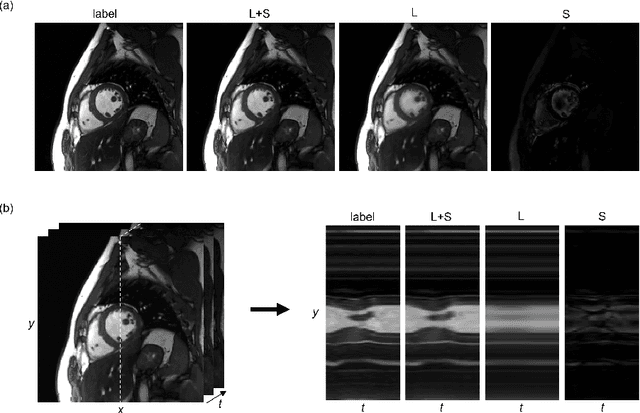

Abstract:In dynamic MR imaging, L+S decomposition, or robust PCA equivalently, has achieved stunning performance. However, the selection of parameters of L+S is empirical, and the acceleration rate is limited, which are the common failings of iterative CS-MRI reconstruction methods. Many deep learning approaches were proposed to address these issues, but few of them used the low-rank prior. In this paper, a model-based low-rank plus sparse network, dubbed as L+S-Net, is proposed for dynamic MR reconstruction. In particular, we use an alternating linearized minimization method to solve the optimization problem with low-rank and sparse regularization. A learned soft singular value thresholding is introduced to make sure the clear separation of L component and S component. Then the iterative steps is unrolled into a network whose regularization parameters are learnable. Experiments on retrospective and prospective cardiac cine dataset show that the proposed model outperforms the state-of-the-art CS and existing deep learning methods.